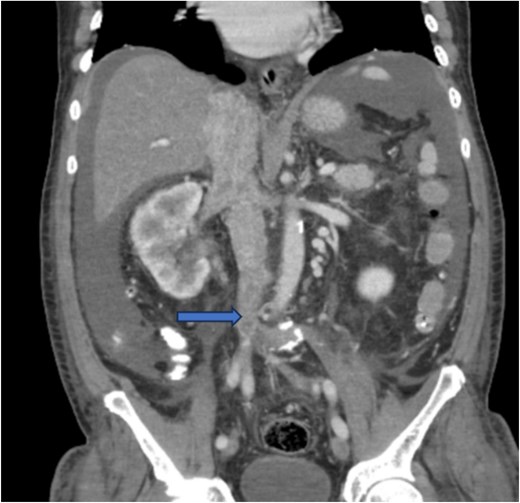

Diagnostic imaging began with a chest X-ray that indicated bilateral pleural effusions. An abdominal ultrasound detected a 4.6 × 4.2 × 4.3 cm echogenic lesion in the right hepatic lobe. Further imaging with a computed tomography (CT) scan of the chest, abdomen, and pelvis revealed a large mass originating from the posterior aspect of the right mid-kidney consistent with RCC (Fig. 1). The mass associated with thrombus extended into the renal sinus and collecting system, traveled along the right renal vein to the inferior vena cava (IVC), and projected into the right atrium (Figs 2 and 3). During hospitalization, bilateral lower extremity pain led to the diagnosis of bilateral deep vein thromboses via duplex venous ultrasound. Echocardiography showed normal left ventricular ejection fraction, impaired diastolic filling, mildly increased ventricular wall thickness, and an echogenic mass extending from the right atrium into the IVC consistent with the tumor thrombus.

CT chest abdomen and pelvis with contrast showing middle portion of right with tumor during venous phase venous phase.